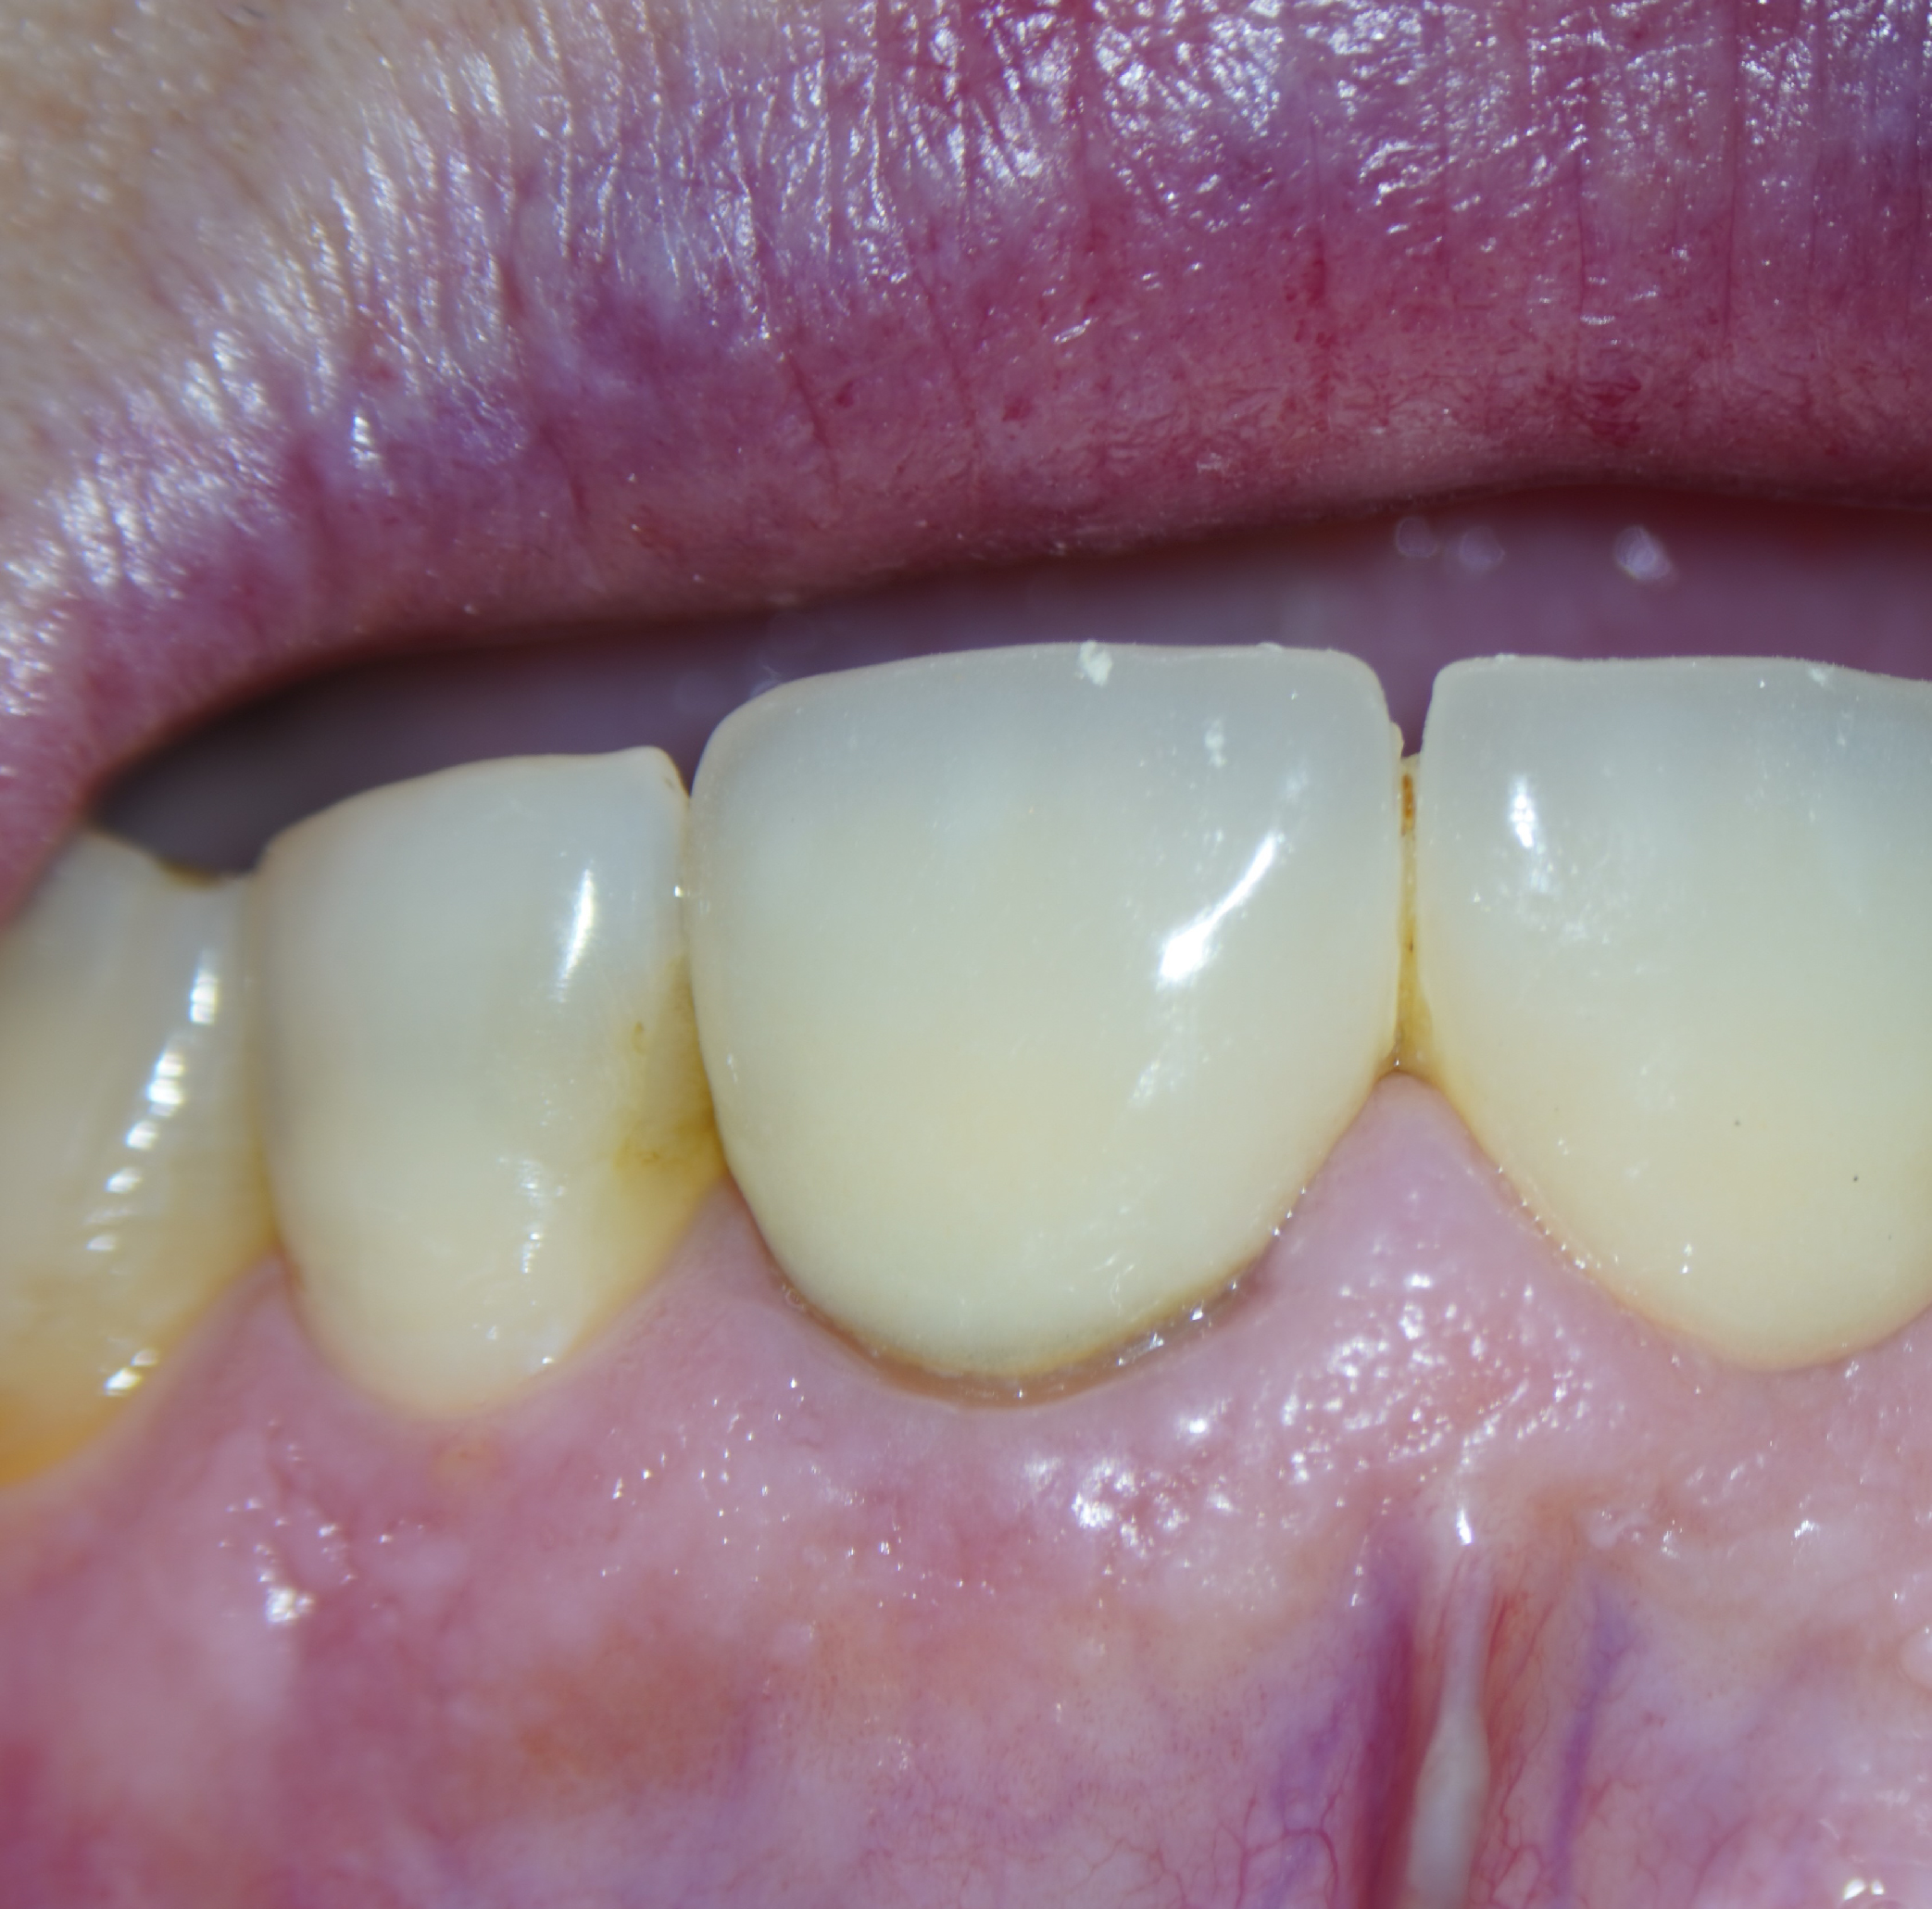

Imágenes del tratamiento

* Haz click sobre las imágenes para verlas a mayor tamaño y a color